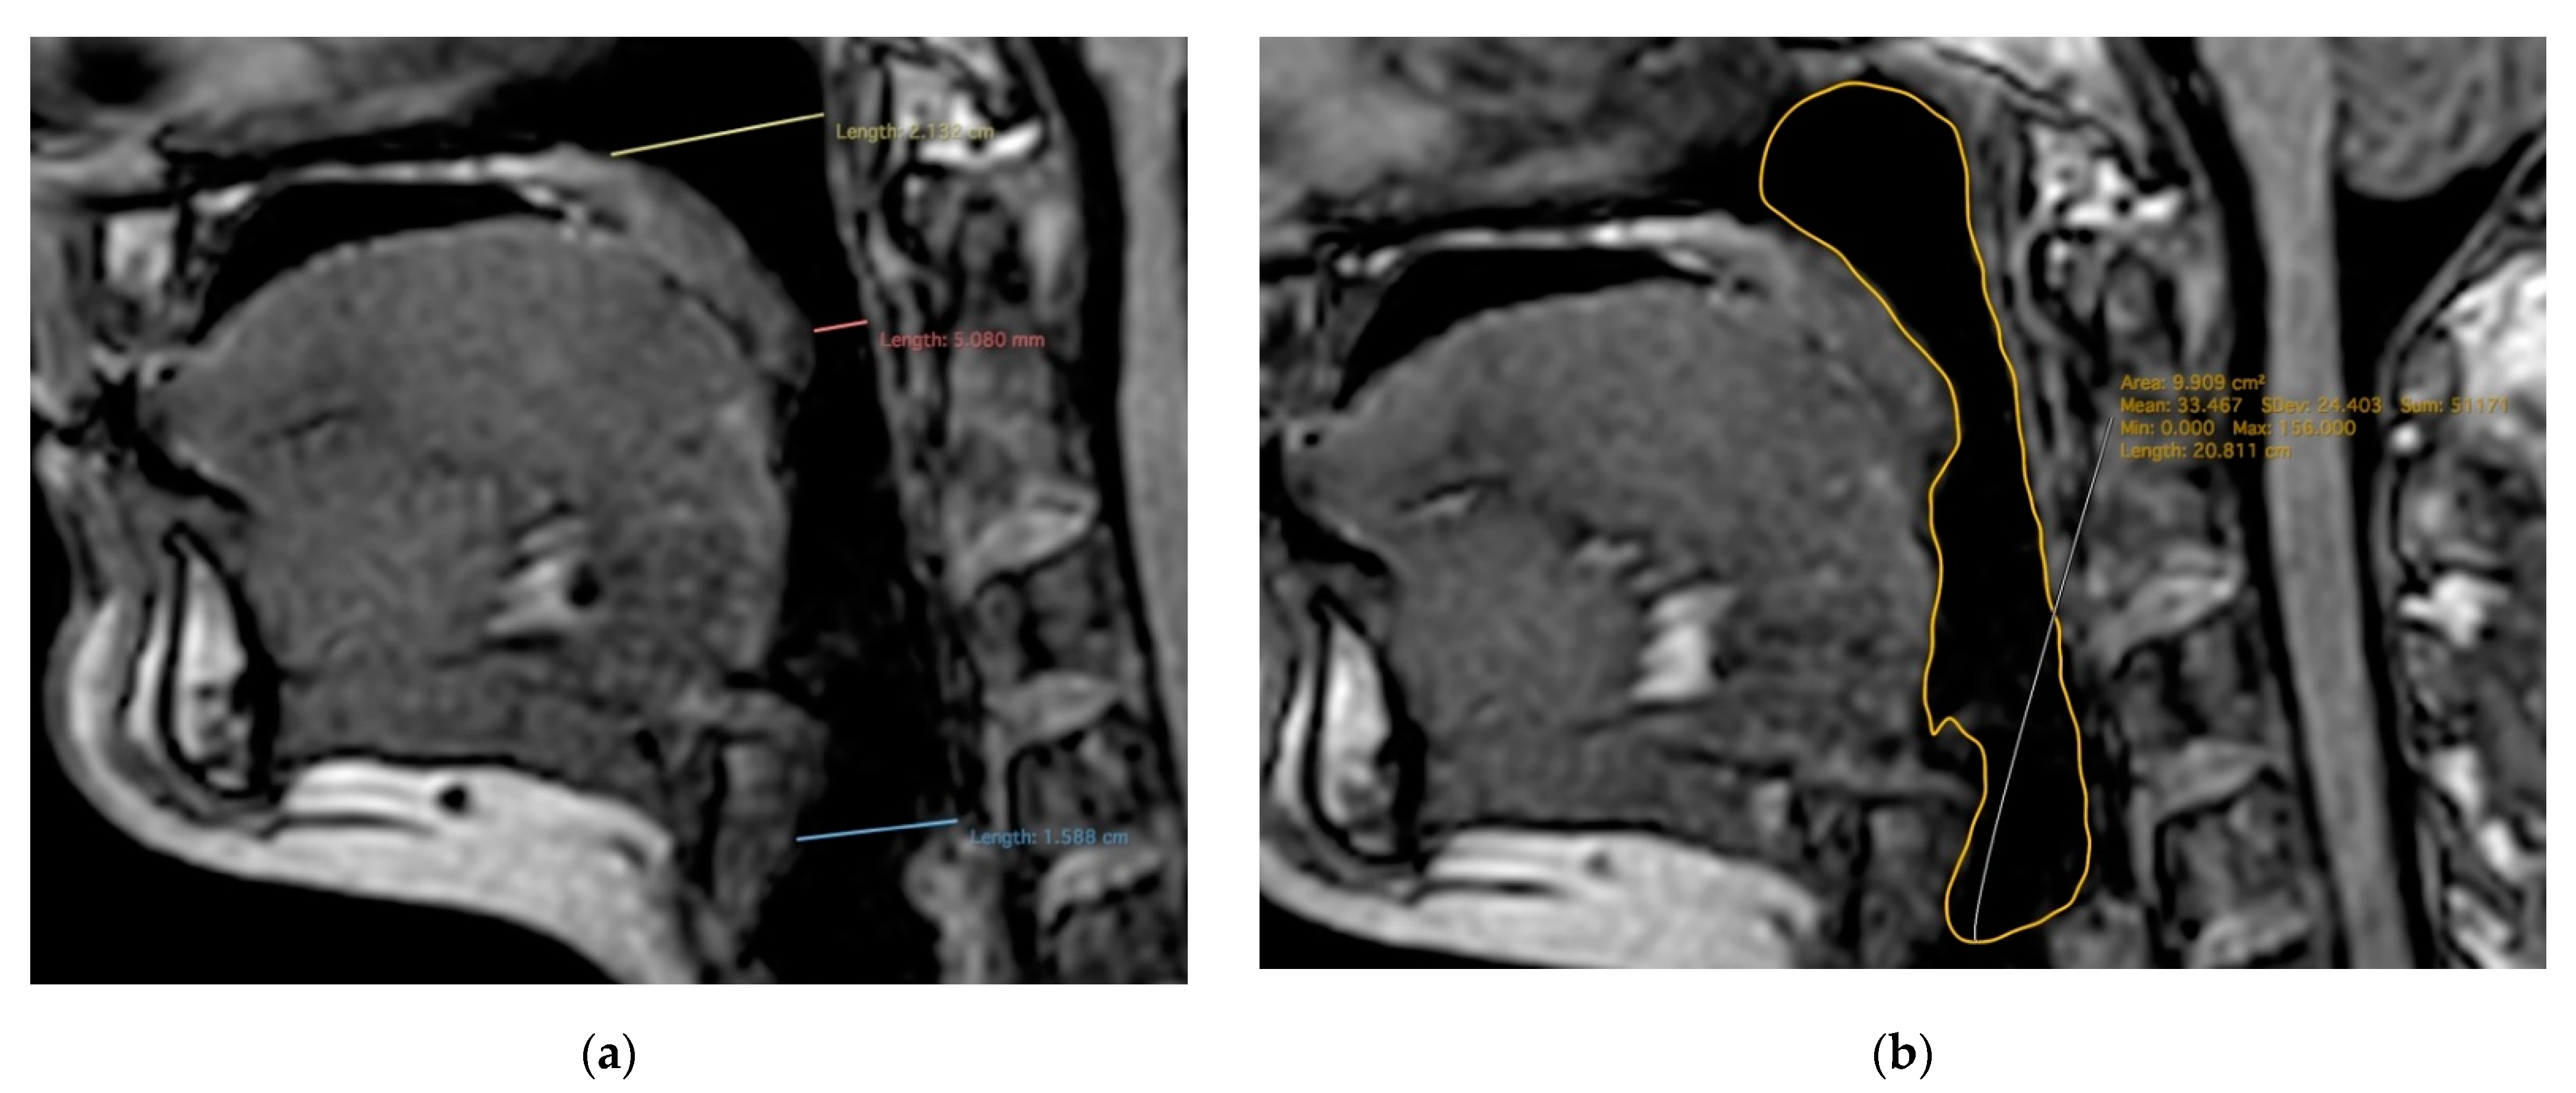

2.2. MR Imaging